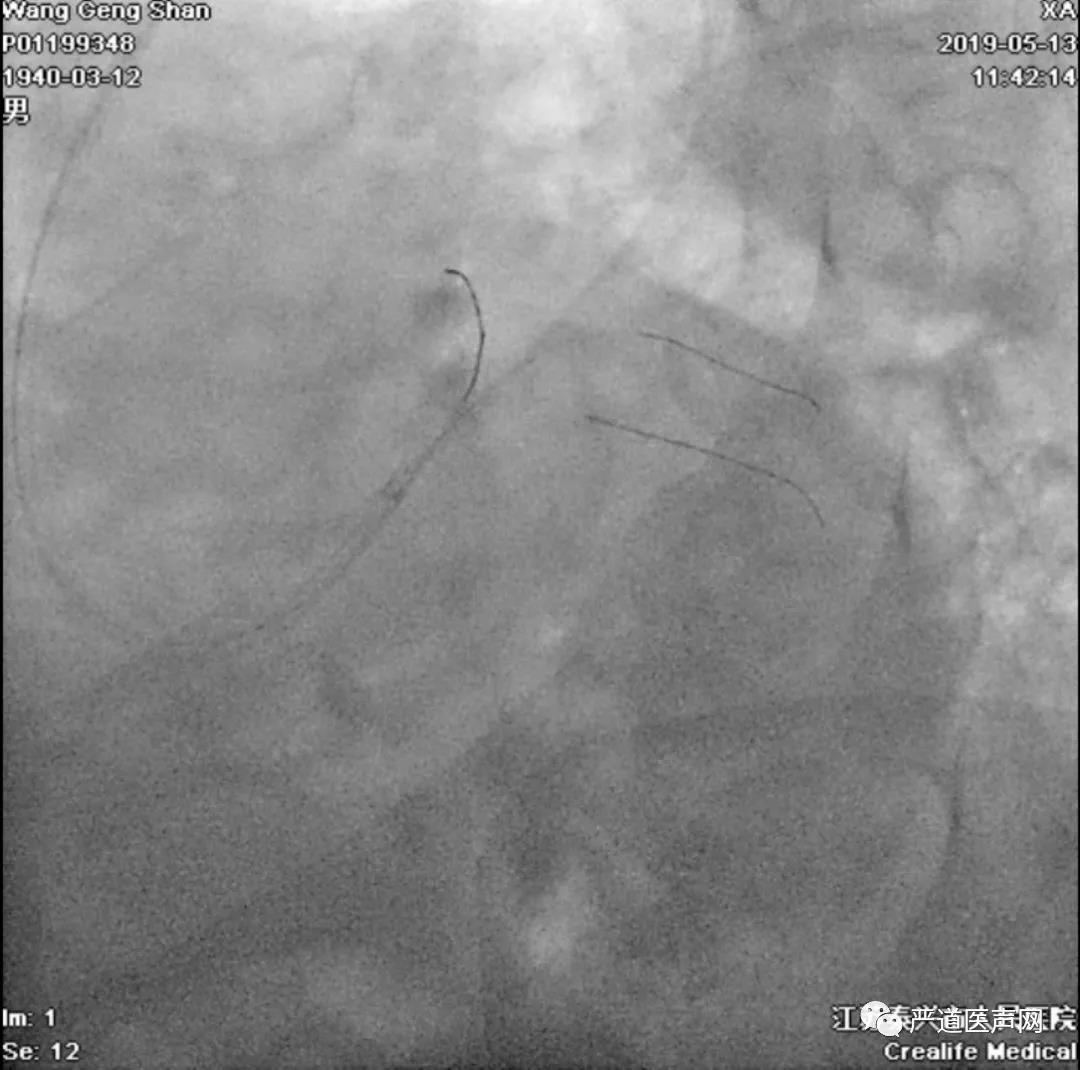

左冠共计5根导丝